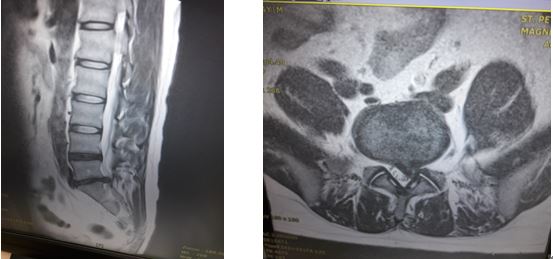

척추와 뼈 사이에 위치한 이 디스크는 외부로부터의 물리적 충격을 완화하고 단단한 뼈가 직접 충돌할 때 문제가 발생하지 않도록 하는 탄성이 높은 구조입니다. 외부의 영향이나 잘못된 위치로 인해 디스크가 꺼지면 염증이 발생하고 신경이 눌려 요통과 요통이 발생합니다. 기술적으로는 요추 디스크 분리라고 하며 일반적으로 요추 디스크 고장이라고 합니다.

허리디스크 진단법

몇 가지 수술적 치료법이 있습니다. 복부 절개를 제거하기 위해 신경을 누르는 리본을 제거하는 수술이 있습니다. 허리를 잡은 상태에서 척추를 떼어내는 척추융합술도 있습니다. 마지막으로 레이저로 디스크를 제거하는 레이저 절제술이 있습니다.